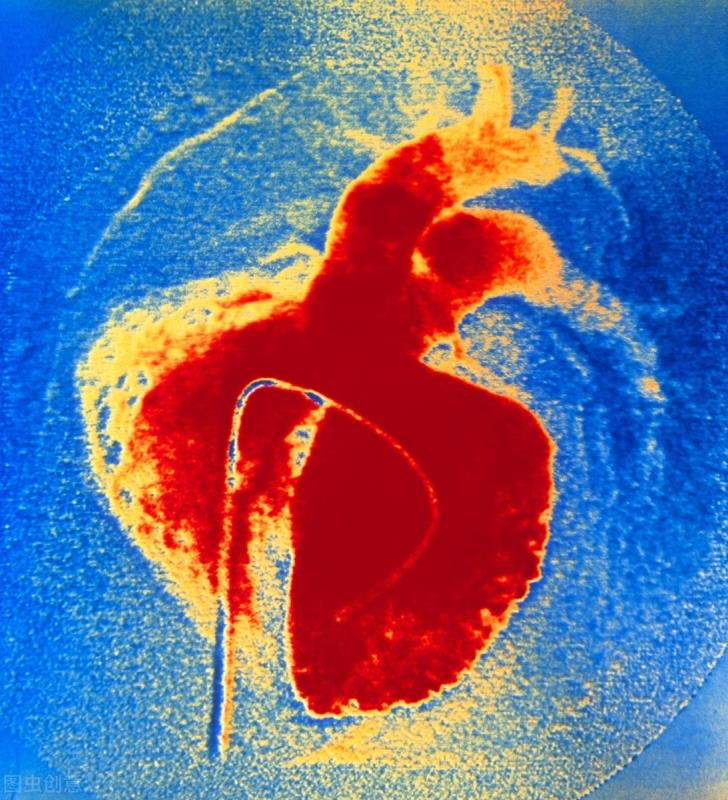

室间隔缺损是一种常见类型的先天性心脏病,指的就是人体左、右心室之间有一个“交通”,从而引起血液经过这个“缺损”分流,导致心脏负荷增大、肺动脉高压等,大多数需要手术治疗。室间隔缺损并没有遗传性,不必或许担心。为了具体的了解室间隔缺损,我们来学习以下几个方面:

室间隔缺损:老死不相往来的兄弟开了窗

- 左右两边不相通:我们正常人的心脏分左右两边,左边和右边都分别有心房和心室,左心室(哥哥)和右心室(弟弟)之间被室间隔隔开,这个是间隔是一块心肌组织,正常人的是间隔厚度一般在10毫米左右,左心室和右心室之间的血液是不会直接沟通的。

- 两边压力不一样:左心室是大哥,比较强壮,它提供的是体循环的动力,就是我们平常所测量的动脉压,一般在90~120mmHg。右心室是小弟,比较薄弱,它提供的是肺循环的动力,一般小于30mmhg。

- 室间隔缺损:在室间隔的任何一个部位都有可能发生缺损,根据这个“窗户”开的位置不一样,把室间隔缺损分类为:膜周部、肌部、漏斗部、房室通道等。